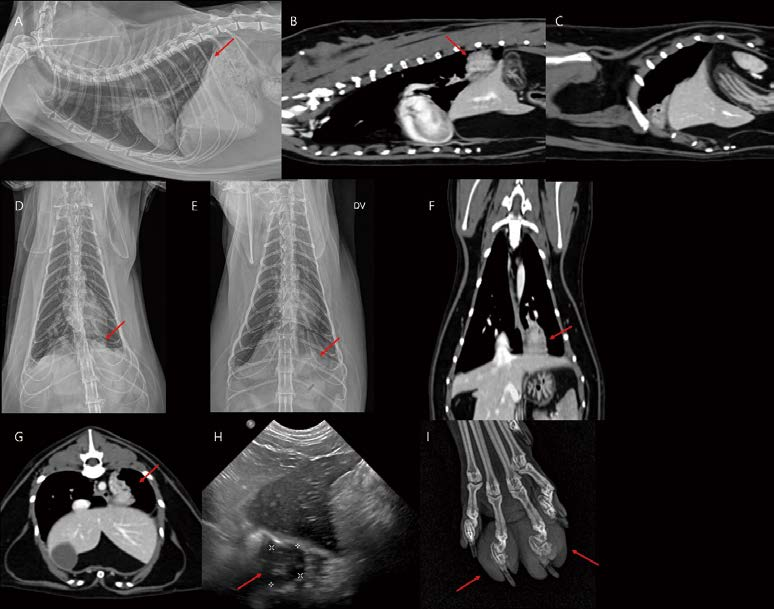

<※증례 ④>

[대한수의사회지 24.png

11살, 중성화 수컷, 5.1kg, Persian cat이 호흡곤란으로 내원했습니다. 흉부 방사선 검사에서 다량의 흉수가 관찰됩니다. 모든 폐엽은 round contour를 보입니다(A, B). 흉수 천자 시 감염 없는 유미흉으로 확인되었습니다. 유미흉의 원인을 알기 위해 추가 검사(e.g., CT lymphangiography and angiography)가 필요하나, 보호자님은 일시적인 초음파 가이드 흉수 천자만을 원하셨습니다. 흉수 천자 이후 환자는 호흡이 일시적으로 개선되었습니다(C, D). 그러나, 흉수량은 점점 더 증가하고 폐엽은 더 irregular하게 둥글게 collapse되어 관찰됩니다(E, F). 이번 흉수 천자는 기흉 발생 위험이 충분히 고려되는 상황이었으나, 보호자님의 요청에 의해 진행하였고, 흉수 천자 시작한지 얼마되지 않아, 환자는 기흉 발생으로 호흡 곤란이 더 심해졌습니다(G, H, 붉은 화살표). 이제 흉수와 기흉(spontaneous pneumothorax)이 혼재되어 호흡 곤란의 임상 증상이 조절되지 않는 상태가 되었고(G, H), 일주일 이내 사망하였습니다.

다음 환자도 idiopathic chylothorax(A, CT lymphangiography)로 진단된 고양이입니다. 안정적인 마취를 위해 흉수 천자를 소량 진행하고 촬영한 흉부 방사선 검사에서 소량의 기흉이 고려됩니다(C, E). CT 검사에서 폐엽 말단 부위에서 small parenchymal consolidation 영역 및 visceral pleural thickening이 관찰됩니다(노란 화살표). 이 주변으로 소량 기흉이 관찰됩니다(붉은 화살표). Idiopathic chylothorax + Fibrosing pleuritis + Spontaneous pneumothorax 상태라 할 수 있겠습니다. 보호자님이 Idiopathic chylothorax 수술적 교정은 원치 않으셨고, spontaneous pneumothorax 정도가 미약하여, 의뢰 병원에서 어느 정도 관리 중이라고 하였습니다. 고양이 흉수에서 폐엽의 irregular 정도, round contour 정도 평가는 환자의 예후에 매우 중요한 정보이며, 흉부 방사선에서도 어느 정도 평가가 가능하므로, 세밀한 판독이 추천됩니다.